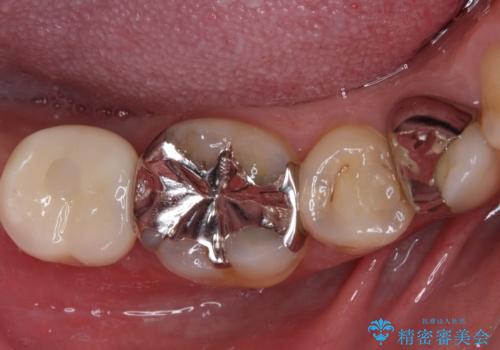

- 下顎左右の奥歯を治療途中で放置してしまっているとのことで来院された患者様です。

欠損部はインプラントによる補綴治療を、土台の外れてしまった歯は、根管治療を行った上で、補綴治療を行うこととしました。

骨格的に下顎が大きく上顎が小さいため、奥歯に力の負担のかかりやすい咬み合わせであるので、治療後は睡眠時にマウスピースを装着することで、セラミッククラウンやインプラント、治療をしたご自身の歯が長持ちするよう指導しています。